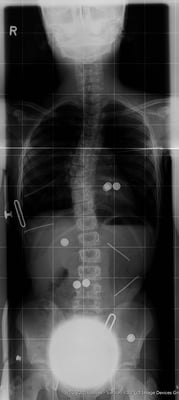

Bildlegende, von links: Röntgen mit Korsett, Röntgen von vorne/seitlich, Röntgen mit ausgeprägter Skoliose